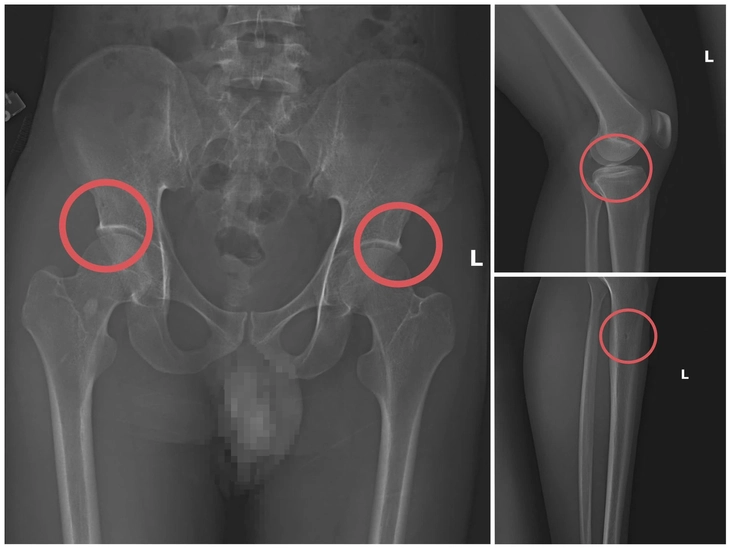

Hình ảnh xương khớp do Châu gây thương tích để chiếm đoạt tiền bảo hiểm nhân thọ - Ảnh: Công an tỉnh Phú Thọ

Lợi dụng thời gian dài công tác trong ngành y và am hiểu sâu cấu tạo xương - khớp, cũng như cơ chế chi trả bảo hiểm đối với các thương tích gãy xương giá trị cao, Châu đã dựng lên một quy trình trục lợi bài bản, từ việc vận động mua bảo hiểm, tổ chức gây thương tích, đến hợp thức hóa hồ sơ bệnh án để chiếm đoạt tiền của các công ty bảo hiểm.

Đáng chú ý, Châu trực tiếp thực hiện hành vi tiêm thuốc mê, rồi dùng kim tiêm, búa, đinh để tác động vào xương người mua bảo hiểm, tạo nên các vết nứt, vỡ xương tương tự tai nạn thật.